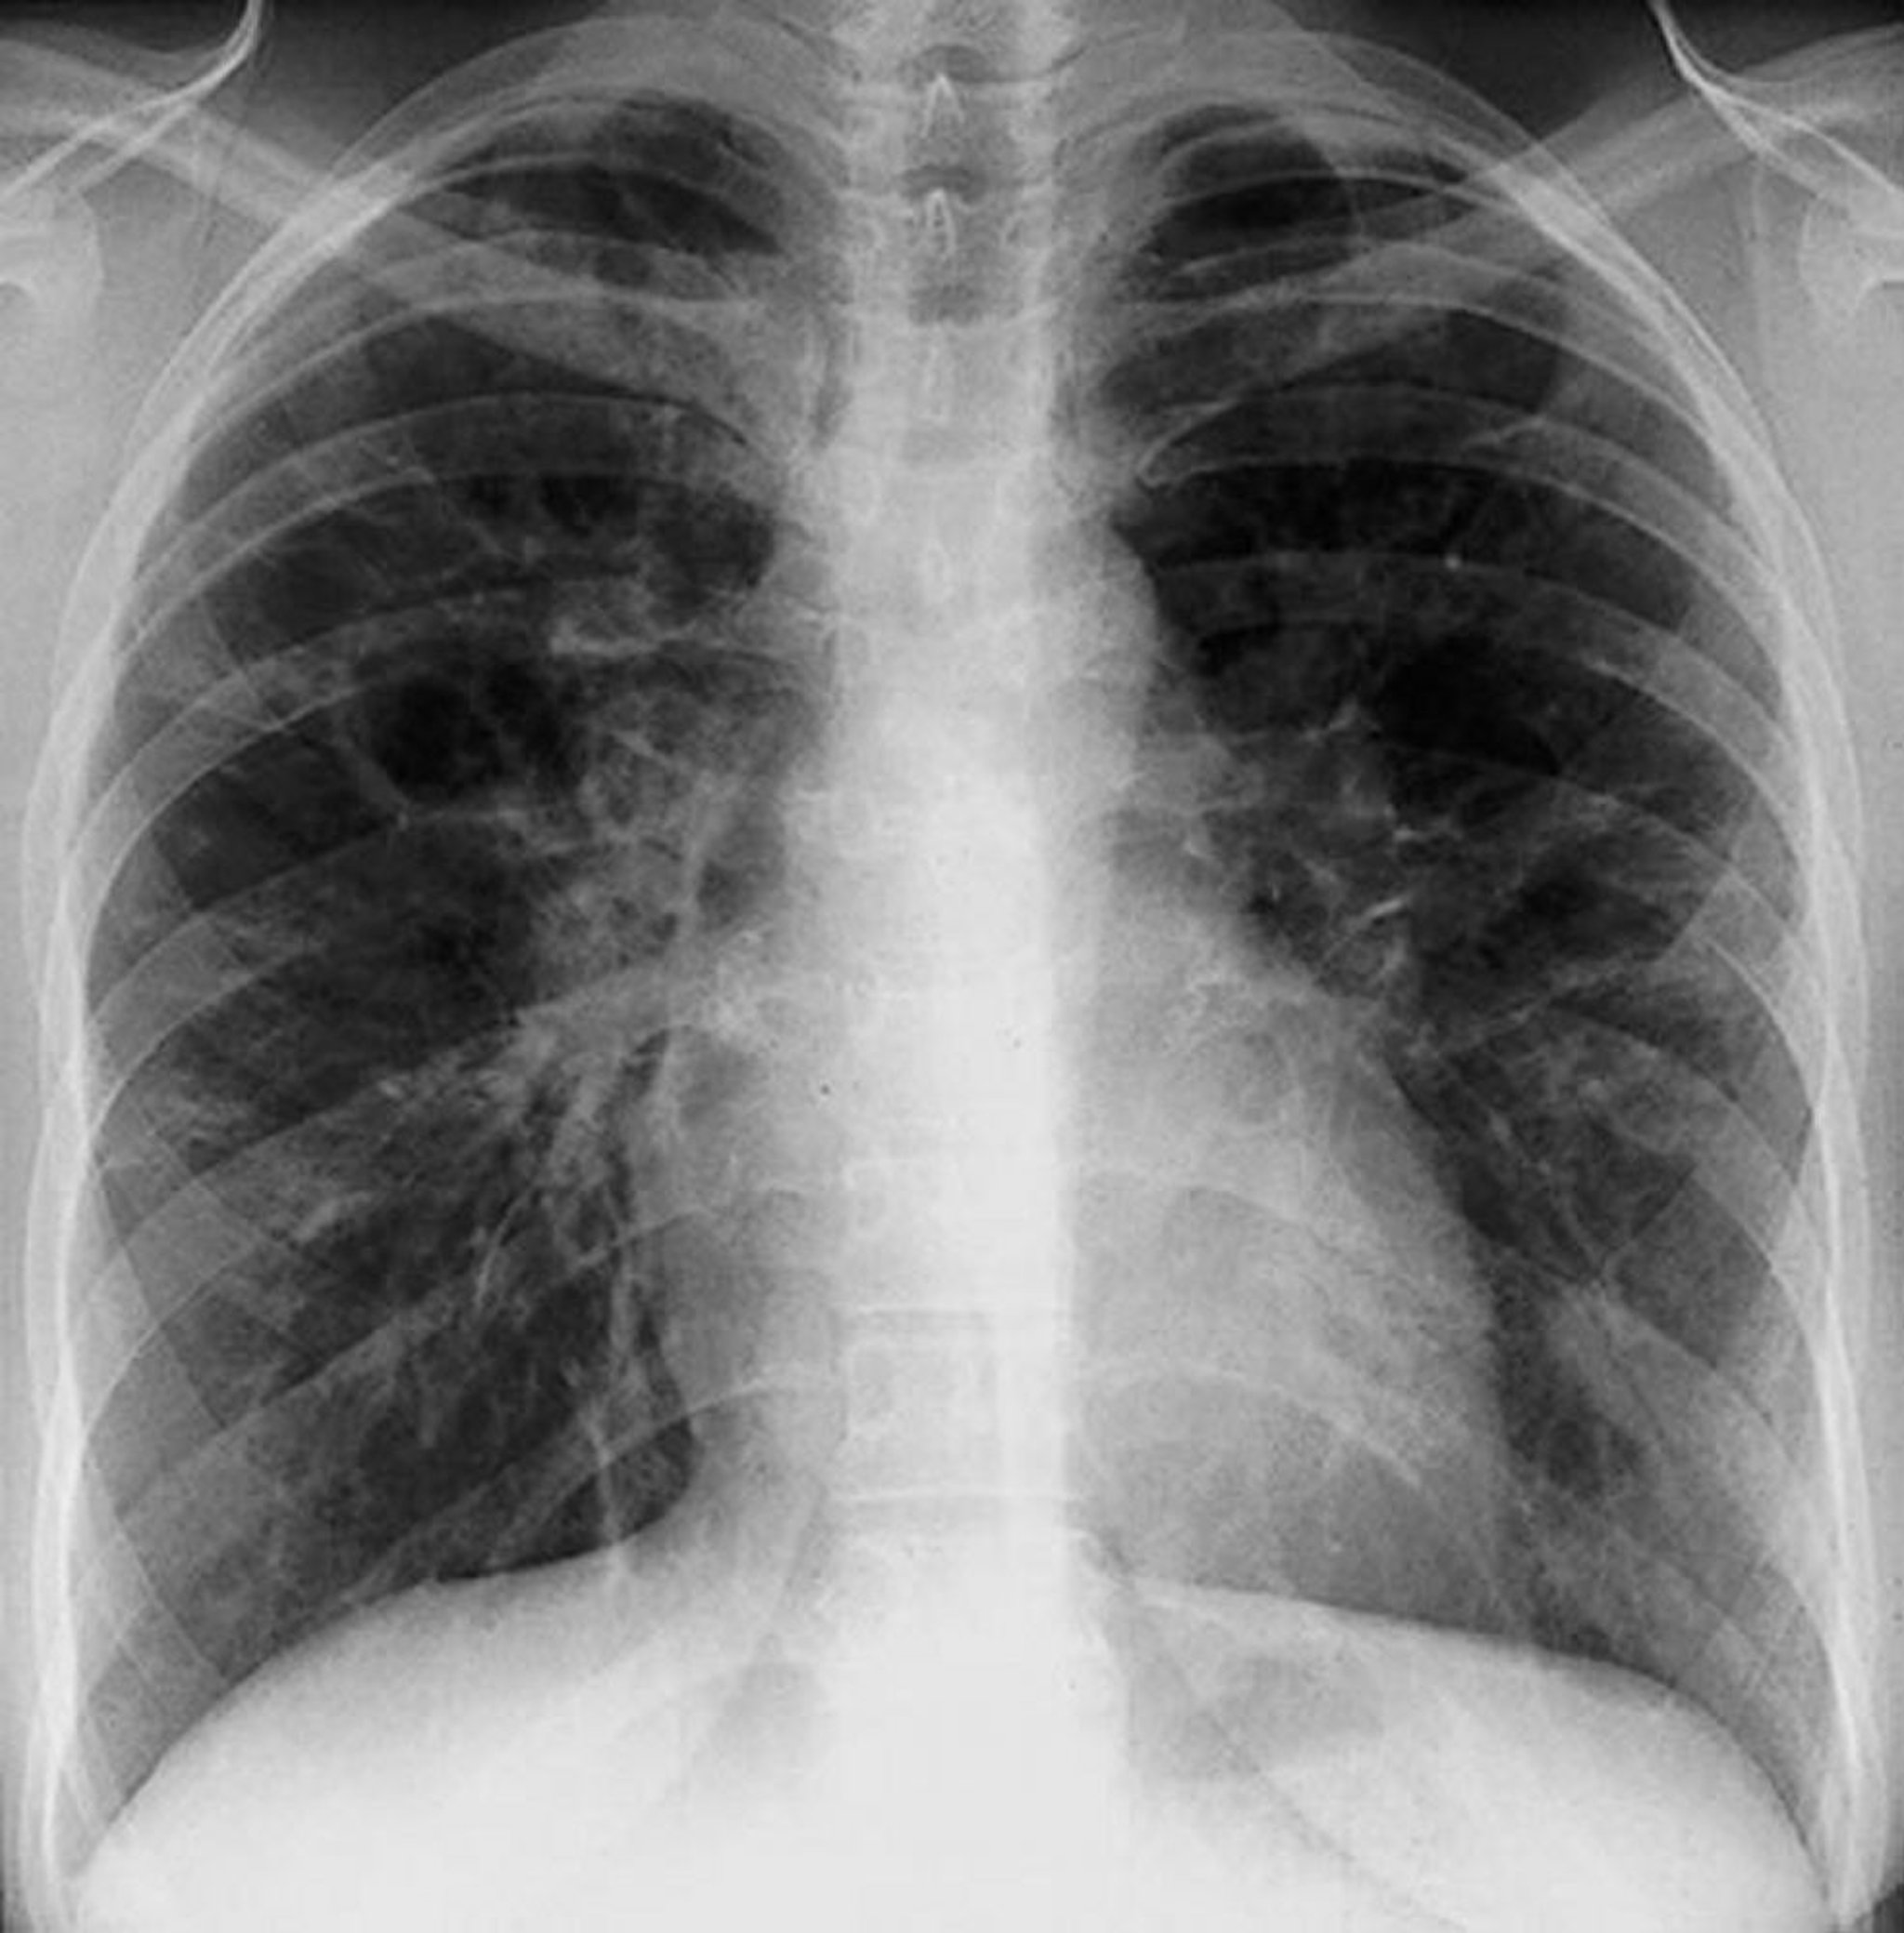

Sarcoïdose (stade III)

Opacités interstitielles diffuses sans adénopathie hilaire dans la sarcoïdose de stade III.

By permission of the publisher. D'après Tanoue L, Elias J. In Bone's Atlas of Pulmonary and Critical Care Medicine. Edited by J Crapo. Philadelphia, Current Medicine, 2005.